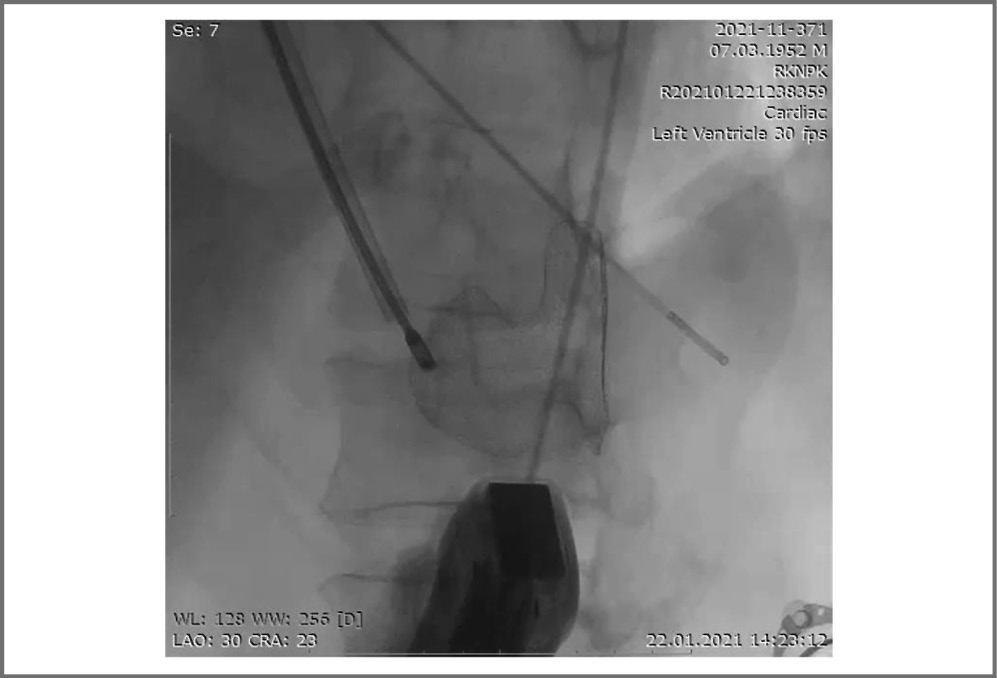

Учитывая тяжесть состояния пациента, консилиумом Heart Team принято решение об экстренном выполнении закрытия разрыва МЖП эндоваскулярным путем. Пациент переведен в рентгеноперационную. Продолжалась вазопрессорная поддержка норадреналином. Проведена вентрикулография. Определен размер разрыва МЖП – 2,1 см. Выполнено эндоваскулярное закрытие МЖП ОМПП – Flex II ASD Occluder (рис. 4). При ультразвуковом контроле положение окклюдера удовлетворительное, определялся минимальный парапротезный сброс крови слева направо, в полости перикарда свободной жидкости не выявлено. Гемодинамические показатели в пределах нормальных значений (артериальное давление – АД – 105/70 мм рт. ст., среднее – АД 71 мм рт. ст.). Однако во время осуществления гемостаза и наложения давящих повязок у больного наблюдались внезапная остановка дыхания, электромеханическая диссоциация с переходом в асистолию. Проводились реанимационные мероприятия, включая искусственную вентиляцию легких, в течение 35 мин. При повторном ЭхоКГ-контроле – окклюдер стоит в прежней позиции, в полости перикарда визуализируется большое количество свободной жидкости со сдавлением правых камер сердца. Выполнен перикардиоцентез, начато удаление крови из полости перикарда со скоростью активного удаления более 100 мл/мин. При ультразвуковом контроле в полости перикарда сохранялось прежнее количество жидкости.

Рис. 4. Установка окклюдера МЖП.